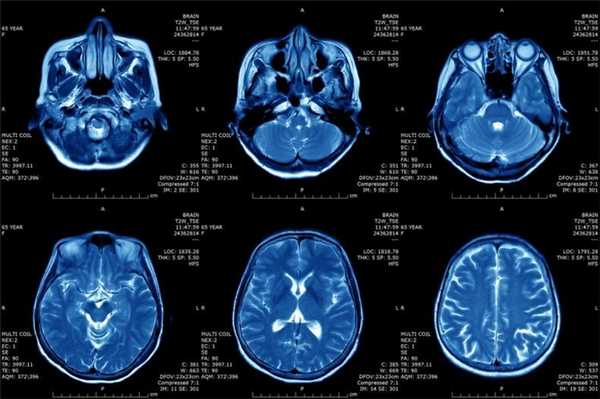

Что показывает МРТ

Магнитно-резонансная томография или МРТ - это сфокусированный метод, который проводит очень детальное обследование. Диагностическая точность МРТ превышает УЗИ и во многих случаях КТ, за исключением сканирования полых органов (легких, желудка, кишечника) и костей. МРТ является золотым стандартом диагностики:

- заболеваний головного и спинного мозга;

- патологий суставов;

- межпозвоночных дисков;

- сердца и сосудов;

- болезней гинекологического, проктологического и урологического характера.

В отличие от быстрого КТ и УЗИ, магнитно-резонансное обследование требует времени - в среднем пациенту нужно лежать в томографе и соблюдать неподвижность 30-60 минут.

Принцип работы МРТ основан на эффекте ядерного магнитного резонанса. МР томограф в своей конструкции имеет мощный магнит, который создает магнитное поле, и датчик, который подает радиочастотные сигналы. В такой ситуации протоны атомов водорода начинают колебательные движения, выделяя при этом импульсы. Их улавливает компьютер томографа и преобразовывает в трехмерные изображения. Чем больше воды содержится в клетках ткани, тем детальней получается ее изображение. Поэтому на МРТ хорошо отображаются органы с большим содержанием воды: МРТ головного мозга, МРТ спинного мозга, МРТ глазных орбит, МРТ органов малого таза, МРТ позвоночника, МРТ суставов, и плохо визуализируются органы с большим содержанием воздуха МРТ органов грудной клетки или кости.

Основы преимуществом МРТ перед КТ и рентгеном является отсутствие в ходе сканирования какого-либо излучения. А вот недостатком этого метода диагностики будет ряд ограничений - наличие ферромагнитного металла в теле пациента и имплантированных в организм водителей ритма, несовместимых с МРТ.